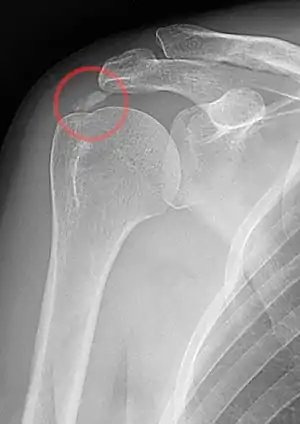

| A plain X ray of the shoulder showing calcific tendinitis | |

An x-ray showing calcific deposits in the area of the tendons of the rotator cuff muscles